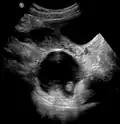

A complex cyst due to a dermoid as seen on ultrasound